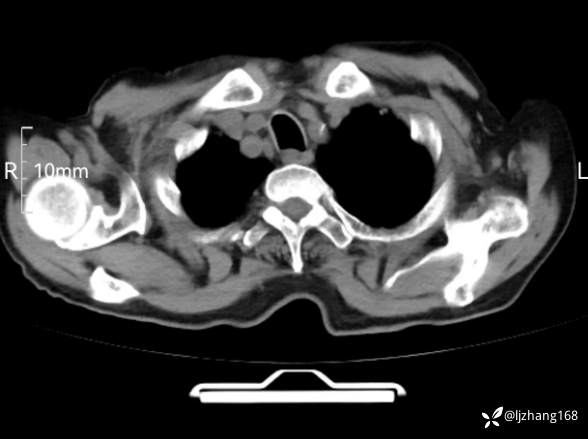

辅助检查:胸部CT:双肺肺气肿,间质性病变,血气分析:PH 7.413, PCO2 29.2mmHg, PO2,81.8mmHg,乳酸 3.3mmol/1,剩余碱-4.0mmol/1,HC03 18.8mmol/1。全血超敏C反应蛋白:超敏C反应蛋白 135.60 mg/L、 白细胞 14x19^9/L,中性粒细胞11.6x10^9/L。